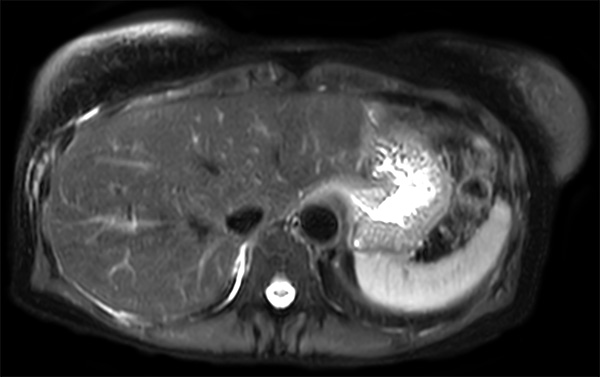

Patient with multiple liver lesions showing up hyperintense on T2-weighted images. The high spatial resolution of MultiVane XD can be appreciated by comparing the images demonstrating the two hyperintense focal liver lesions. mDIXON Quant was performed for quantification of intralesional and hepatic parenchymal fat content. The fat content in the liver parenchyma was normal. The lesion has a fat fraction of 25-30%. Histopathologic diagnosis was hepatocellular adenoma.